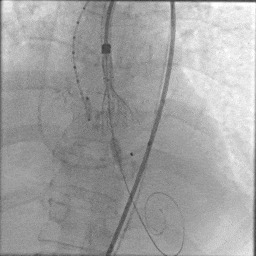

由于患者本身是Type0型二叶瓣,加上钙化较重,给瓣膜植入的位置增加了难度,术中释放多次释放部分回收后,最终释放一个比较满意的位置。

最终定位

最终释放

瓣膜稳步脱钩后,造影显示瓣膜位置合适,冠脉灌注良好,无瓣周漏。

稳步脱钩

最终造影